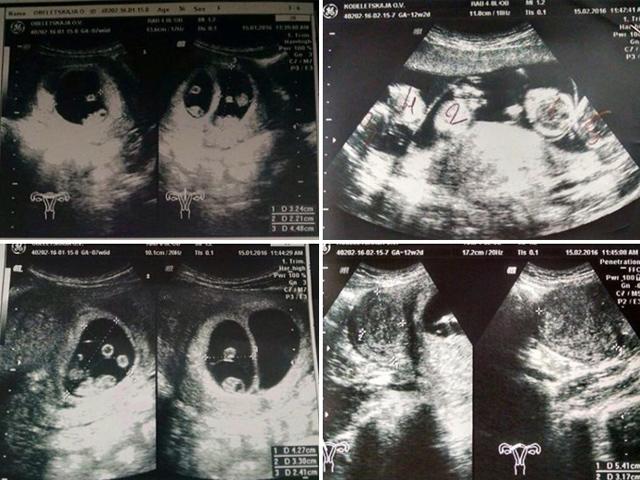

Thế nhưng đến tháng thứ 5 của thai kỳ, kết quả siêu âm cho biết kết cấu tim của thai nhi bất thường như một gáo nước lạnh dội thẳng vào chị Dung. Kết quả siêu âm tiếp theo càng làm mọi người thêm buồn, tâm thất phải không khả quan cho lắm, vị trí động mạch phổi và động mạch chủ đảo ngược.

Em bé trong bụng chị Dung bị phát hiện dị tật tim bẩm sinh.